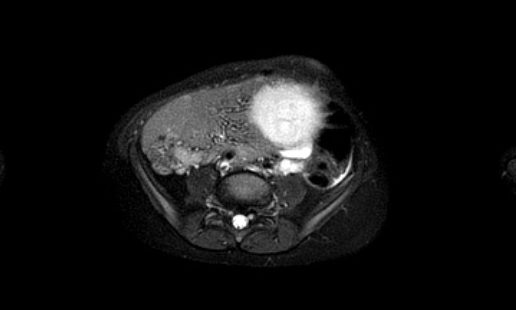

Hình ảnh MRI của một bé gái chín tháng tuổi có khối u ở bụng trái. MRI cho thấy khối u tuyến thượng thận trái, một phần đặc, một phần nang. Có nhiều di căn gan.

Khối u đã được sinh thiết. Có tình trạng chảy máu liên tục qua kim dẫn đường. Vào cuối thủ thuật, hai nút bọt gelatin đã được đặt vào (các dải tăng âm (mũi tên)).